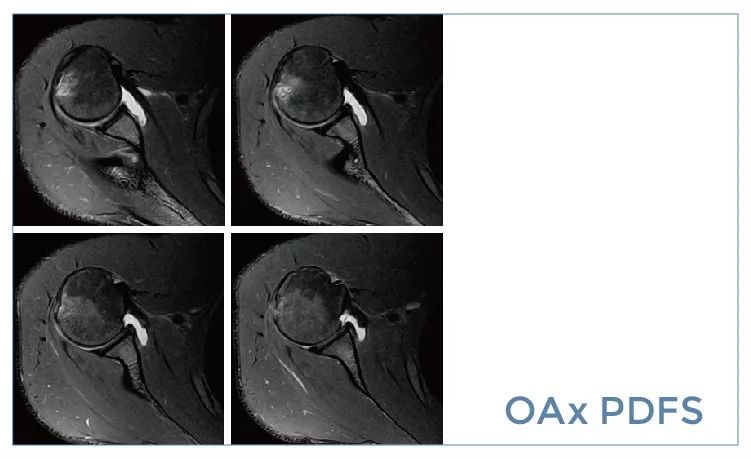

【朗润影像档案】20190927磁共振影像病例结果讨论